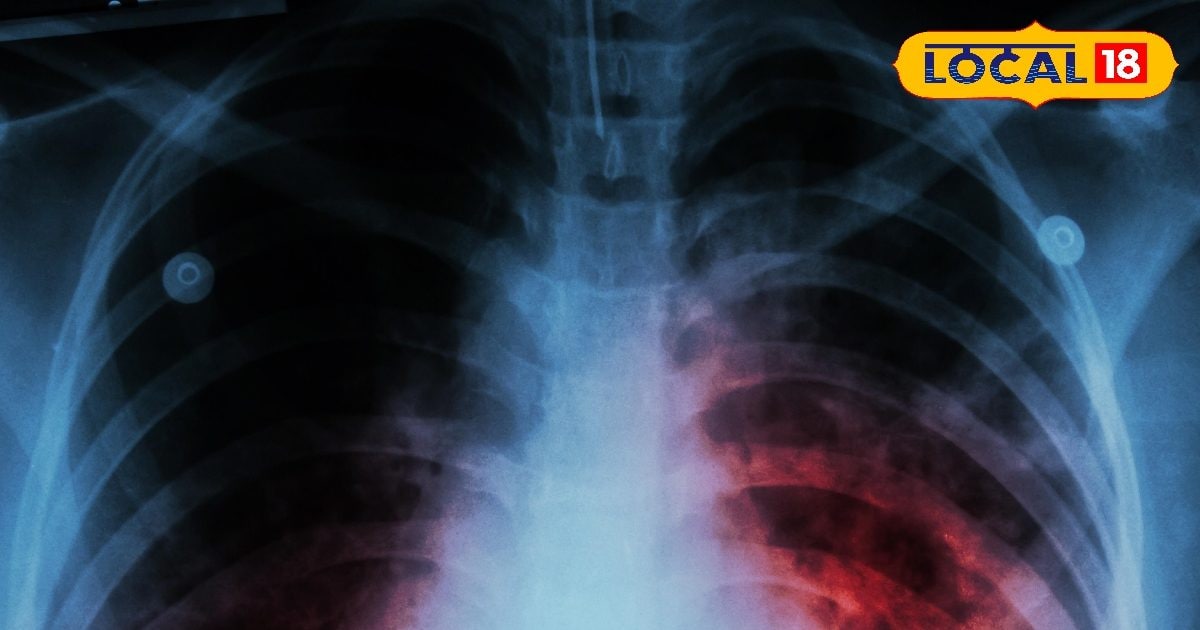

सदर अस्पताल सहित प्राथमिक स्वास्थ्य केंद्रों में ट्रूनेट मशीन की सुविधा शुरू की गई है. यह मशीन टीबी के संभावित मरीज के जांच के लिए प्रयोग की जाएगी. ट्रूनेट मशीन जिले के 16 स्वास्थ्य संस्थानों में लगाई गई है.